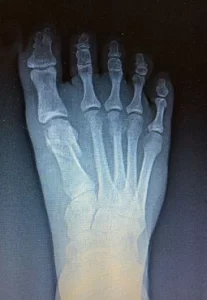

Operación de juanetes: antes y después

JUANETE CON DOLOR CRÓNICO

Paciente con un juanete severo sufría dolor crónico e inflamación persistente que dificultaban su movilidad diaria. Mediante cirugía podológica por mínima incisión, se corrigió la deformidad. En pocas semanas, el paciente volvió a caminar sin molestias, mejorando significativamente su calidad de vida.